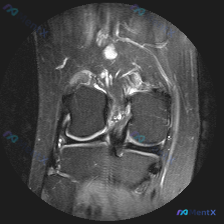

刚看到这个膝关节MRI读片的病例,有点典型,整理出来和大家分享一下思路。 病例基础信息 这是一份膝关节矢状位MRI影像,序列为T2WI或PDWI-FS,对软组织、水肿、韧带病变显示清晰。 影像学核心发现 1. 骨骼与关节软骨:髌骨后方关节软骨面不平整,髌骨软骨下骨可见片状高信号影,提示骨髓水肿或软骨...

刚看到一份膝关节MRI单矢状位切面的读片需求,核心问题是观察半月板异常,我整理了完整的分析思路分享给大家。 一、病例基本影像信息 这是一张膝关节矢状位MRI影像,根据信号特征判断:不符合典型T1加权像(骨髓信号偏低,关节软骨、积液呈高信号),更符合质子密度加权像(PDWI)或T2加权像,这类序列对半...

病例读片分享:临床怀疑半月板异常,单层面MRI怎么看? 今天整理了一份膝关节MRI读片病例,核心问题是临床怀疑半月板异常,但我们拿到的只有一份单冠状位的脂肪抑制序列图像,分享一下我的分析思路。 一、影像基本信息 这是一张膝关节MRI的冠状位脂肪抑制(PD-FS或T2-FS)扫描图像,这类序列对水/液...